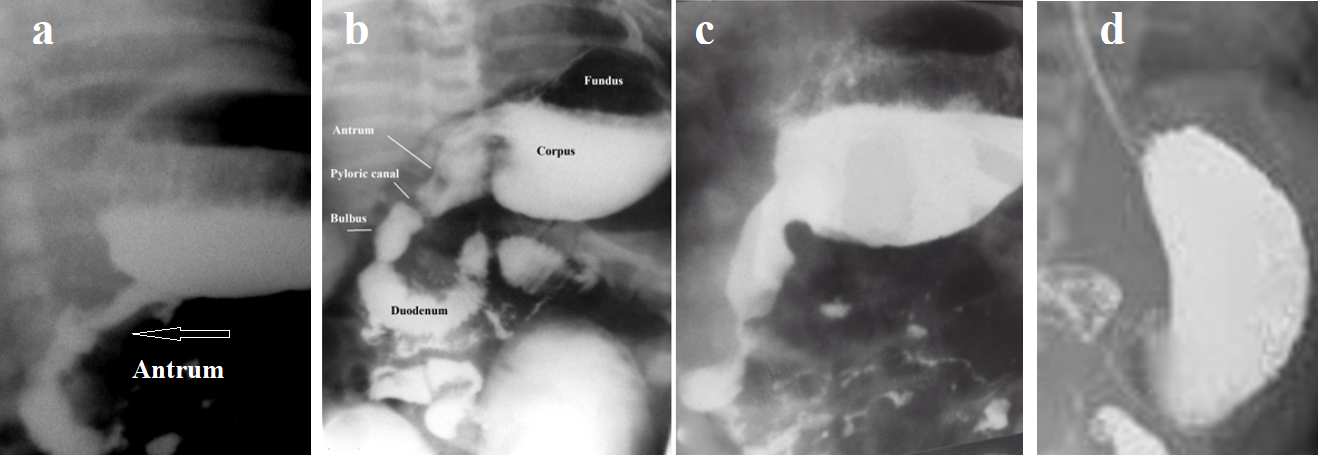

A baby is born with a small stomach. It quickly gains weight because it sucks from 600 ml per day in the first month to a liter of milk in the fifth month. The shape of the stomach in a newborn resembles a retort. Gastric distention begins from the fundus and body of the stomach between the LES and the narrow antral part. In this case, the body of the stomach is located above the bulb of the duodenum. When the antral section expands, the stomach sags below the bulb (Figure 2). The stomach enlarges due to the large volumes of milk consumed. The baby burps up excess milk. If there is no acid in the stomach, it is calm. If acid appears, it causes damage to the esophagus, which is accompanied by pain. That is why the baby cries.

Figure 2. Barium X-ray of the stomach in patients with GERD. (b,c,d,e). Stages of gastric distension in infants.